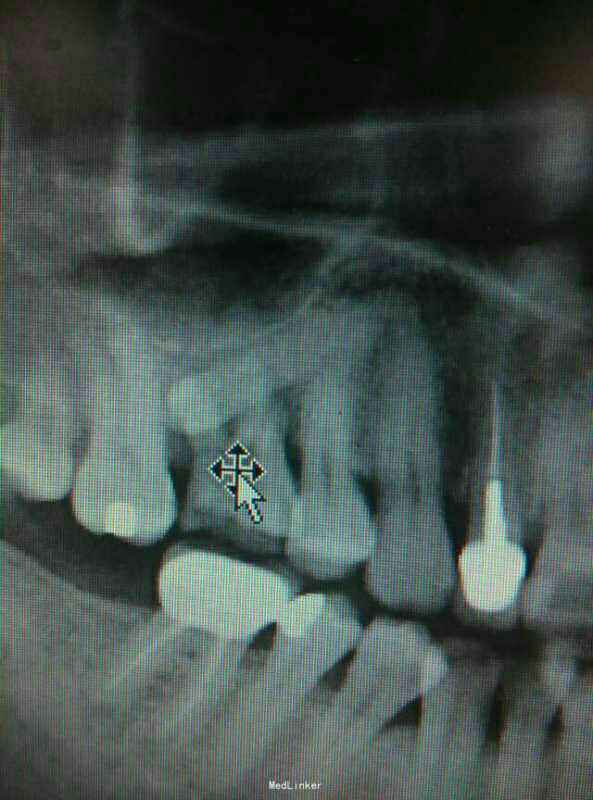

想兼职被要求发病例当代表作,手机里只有今年一月份随手拍下来的当月的几张病例X光片,发出来权当代表作,欢迎大家批评指正。主要是拔牙和根管治疗。

拔牙残根